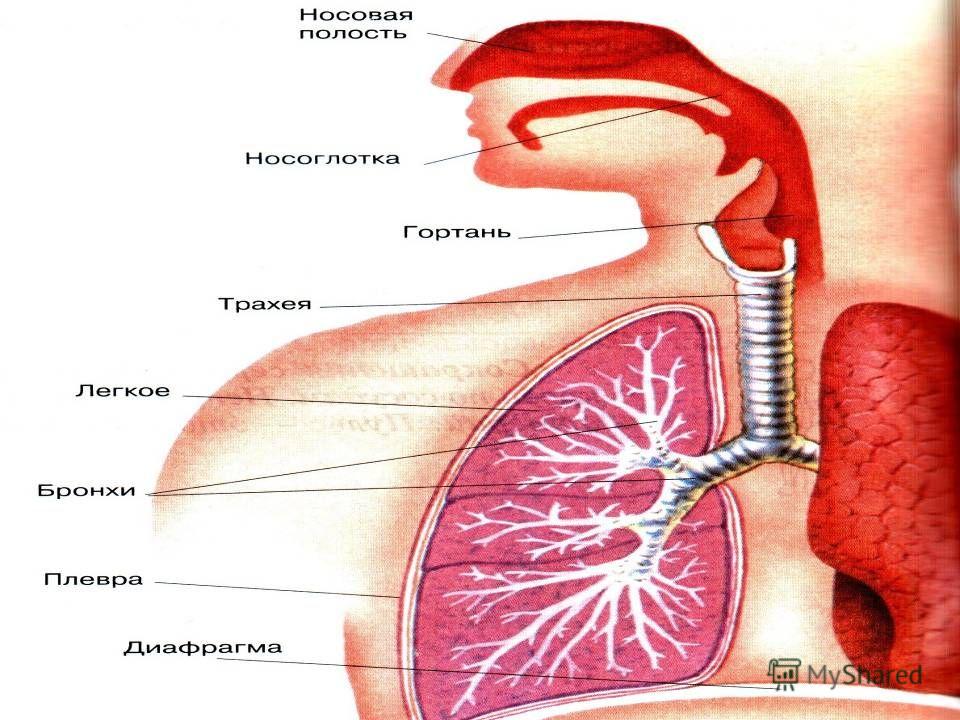

Схема дыхательной системы человека: а — общий план строения; б — строение альвеол; 1 — носовая полость; 2 — надгортанник; 3 — глотка; 4 — гортань; 5 — трахея; б — …

Дыхательные пути представляют собой систему трубок, просвет которых формируется благодаря наличию в них костей и хрящей . Внутренняя поверхность дыхательных путей …

Дыхательнаясистемачеловекасостоитизтканейиорганов,обеспечивающихлегочную вентиляциюилегочноедыхание .К воздухоносным путям относятся: нос, полость носа, носоглотка, …

Дыхательная система (дыхательный аппарат), systema resperatorium, состоит из дыхательных путей и парных дыхательных органов - легких . Дыхательные пути …